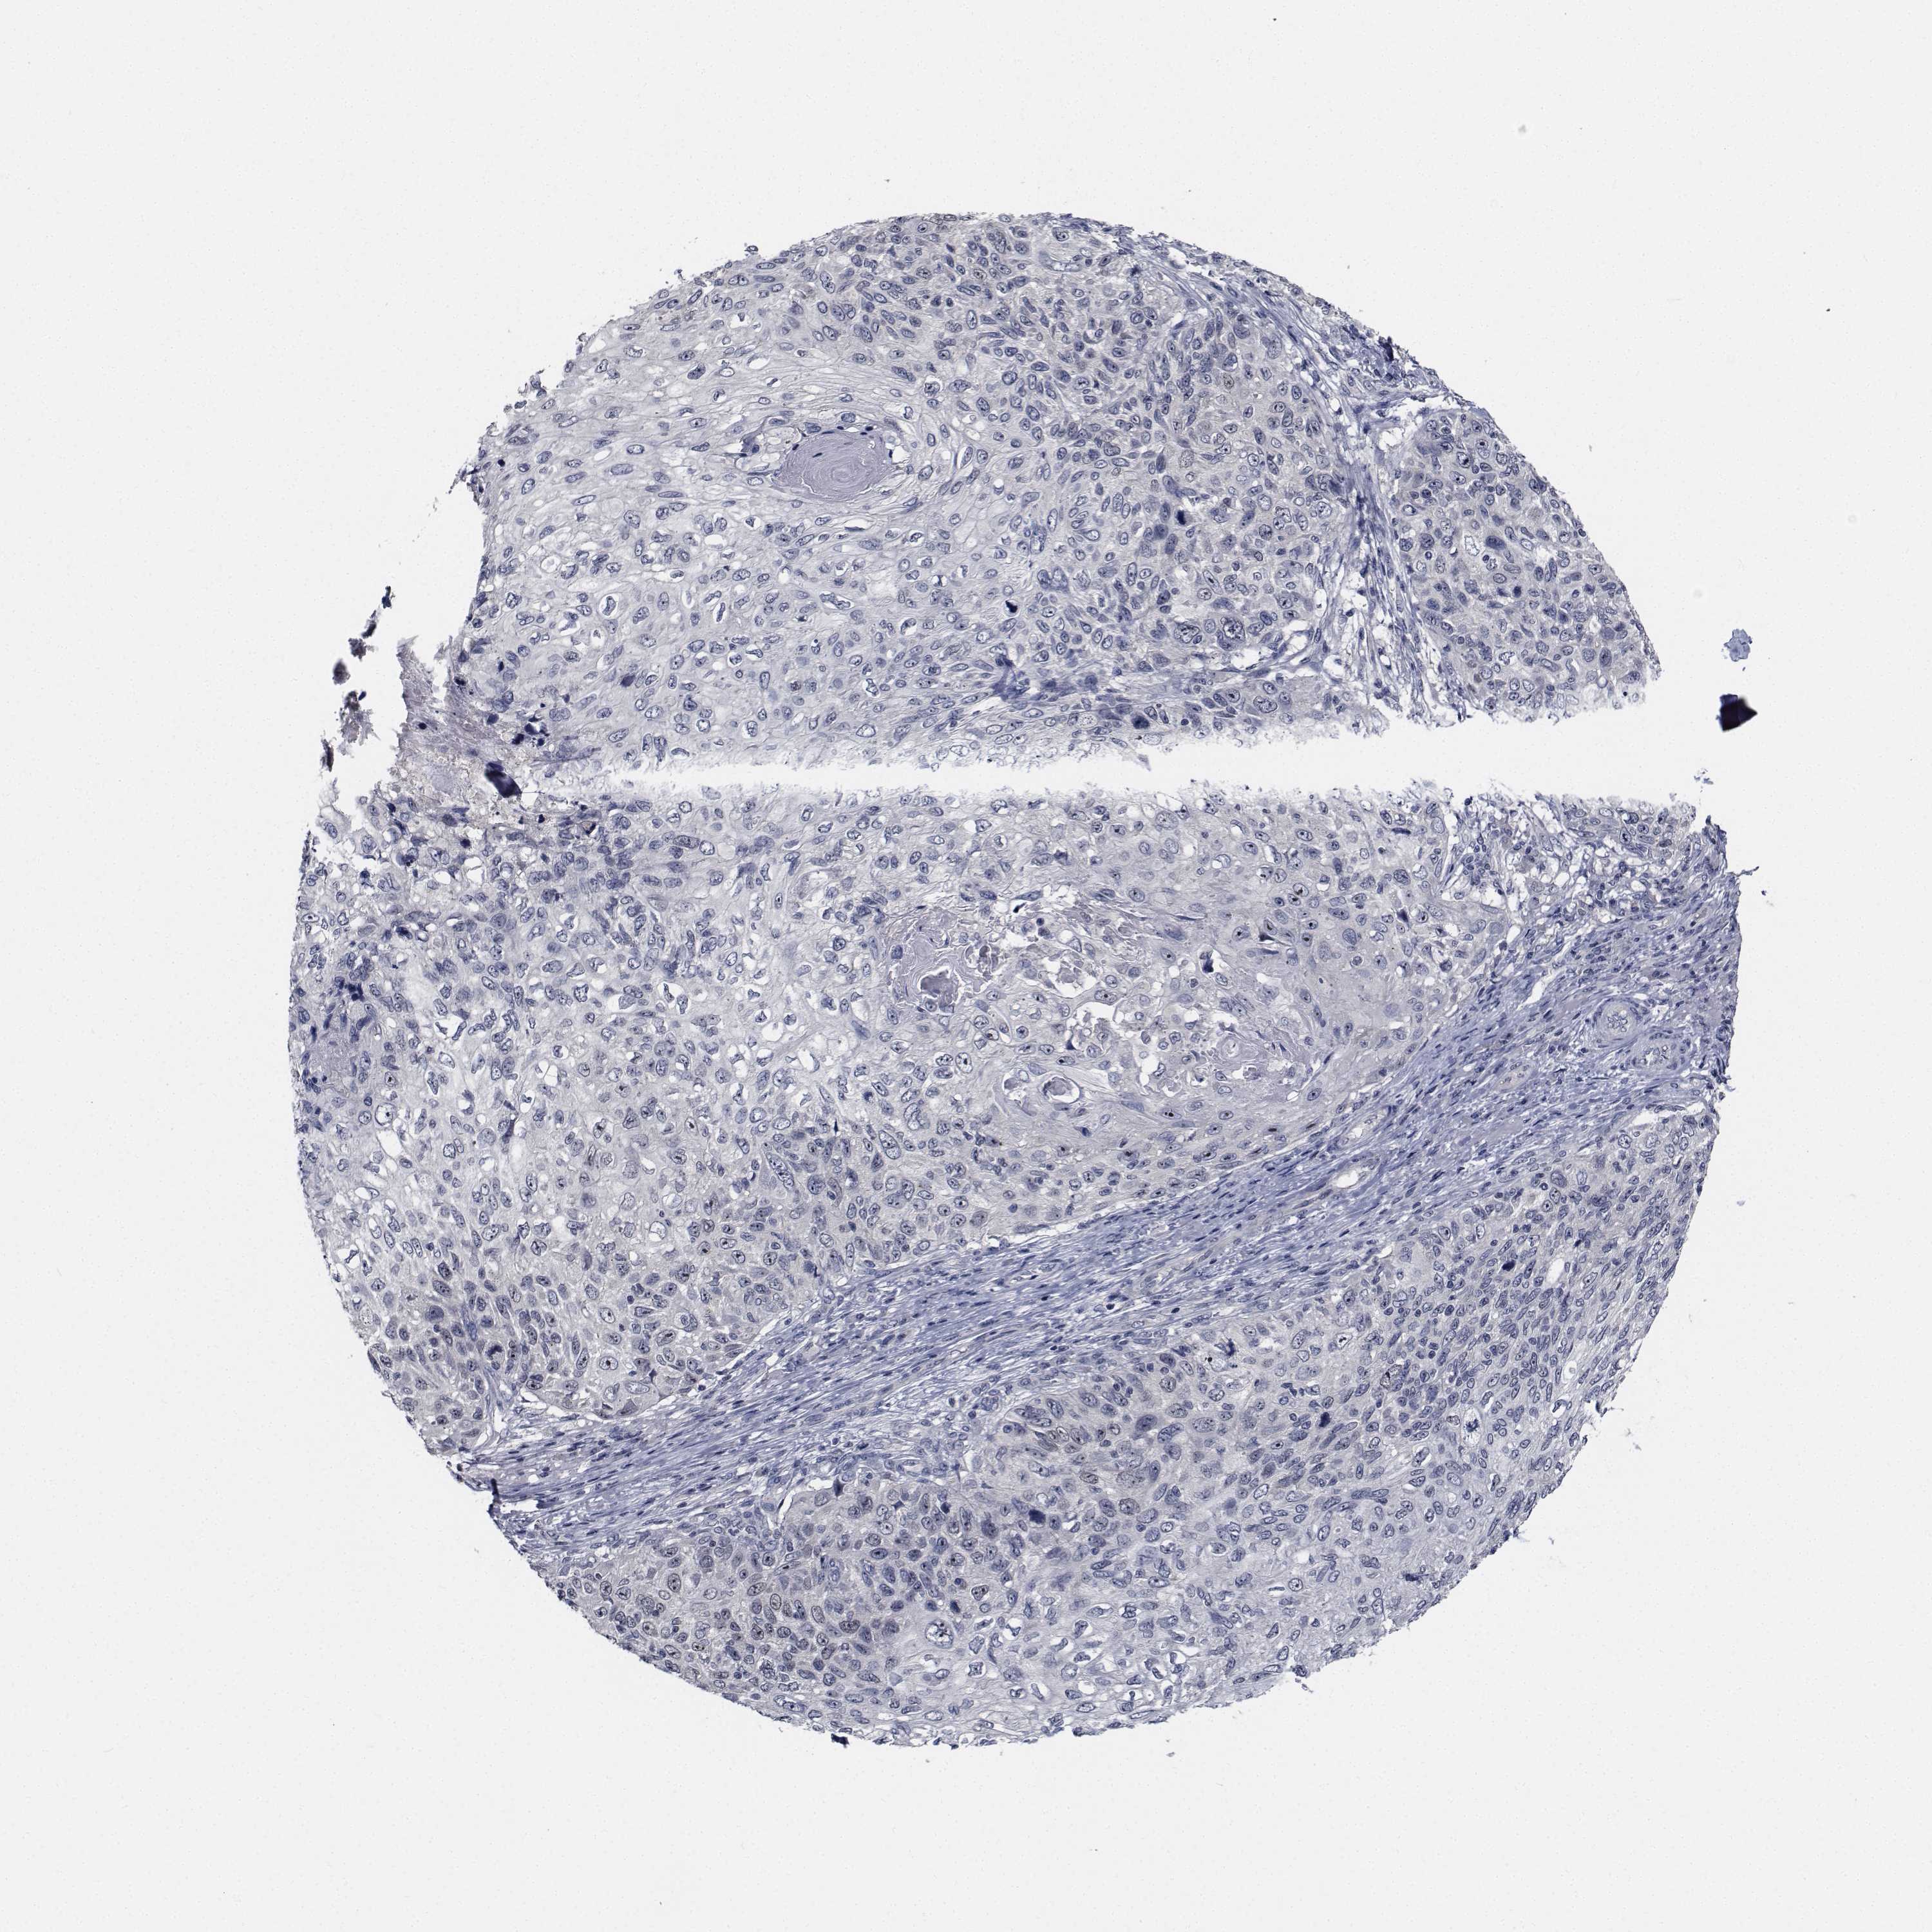

SKIN CANCER - Protein expressioni

A mouse-over function shows sample information and annotation data. Click on an image to view it in a full screen mode. Samples can be filtered based on level of antibody staining by selecting one or several of the following categories: high, medium, low and not detected. The assay and annotation is described here.

Each image is clickable and will lead to virtual microscopy that enables deeper exploration of all samples and also displays staining intensity scores, fraction scores and subcellular localization as well as patient and tissue information for each sample.

Antibody HPA028207

Antibody HPA028224

Antibody HPA028654

Staining

High

Medium

Low

Not detected

Intensity

Strong

Moderate

Weak

Negative

Quantity

>75%

75%-25%

<25%

None

Location

Nuclear

Cytoplasmic/membranous

Cytoplasmic/membranous,nuclear

Basal cell carcinoma

Squamous cell carcinoma, NOS